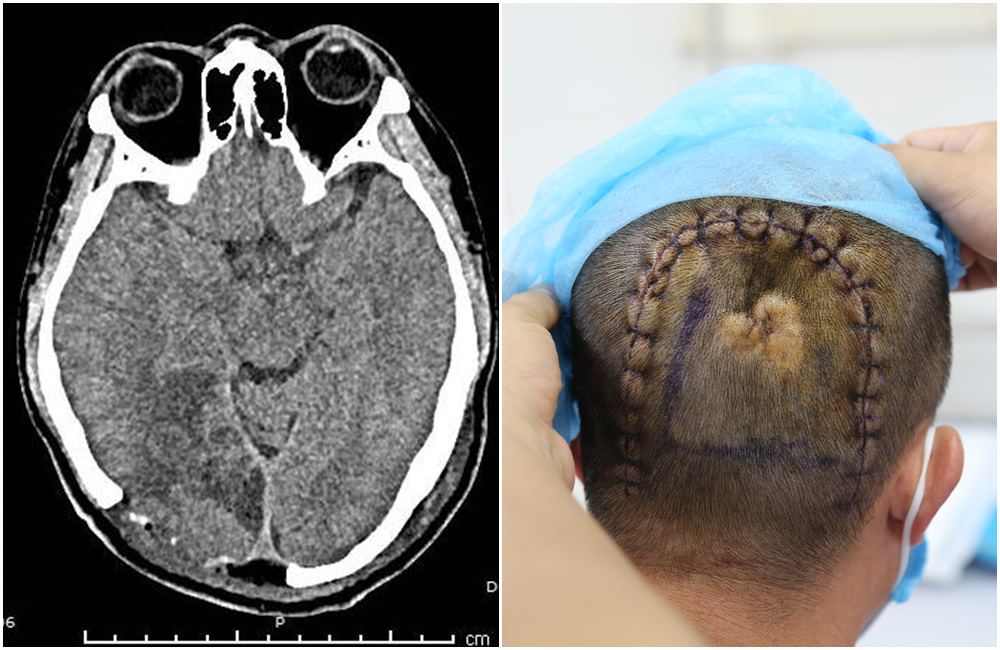

Bệnh nhân là N.V.K (44 tuổi) ở xã Nam Sơn, huyện Ba Chẽ. Trước đó, bệnh nhân bị tai nạn ngã cao 2m đập đầu xuống nền cứng, sau khi sơ cứu tại Trung tâm y tế tuyến dưới được chuyển lên Bệnh viện Đa khoa tỉnh. Kết quả thăm khám và chụp cắt lớp vi tính kiểm tra thấy hình ảnh đụng dập nhu mô não trán trái, đồng thời phát hiện khối u não lớn vùng chẩm, kích thước khá lớn. Các bác sĩ chẩn đoán bệnh nhân bị chấn thương sọ não, u não chẩm phải. Sau khi hội chẩn, các bác sĩ quyết định điều trị chấn thương sọ não ổn định và hẹn phẫu thuật xử trí u não.

Hình ảnh khối u não kích thước lớn của bệnh nhân K.

Sau 1 tháng, bệnh nhân ở nhà xuất hiện tình trạng chóng mặt, đau đầu nhiều nên nhập viện. Các bác sĩ chụp cắt lớp kiểm tra thấy khối u não chẩm phải kích thước 6x7cm nằm sát đường giữa, xung quanh phù não nhẹ. Đánh giá khối u não đã lớn, lại có dấu hiệu chảy máu gây phù xung quanh, nguy cơ biến chứng nguy hiểm, có thể tử vong nếu không được phẫu thuật xử trí kịp thời. Các bác sĩ đã chỉ định phẫu thuật vi phẫu u não đường giữa cho bệnh nhân K.

Kíp bác sĩ chuyên khoa phẫu thuật thần kinh đã tiến hành mở xương sọ, màng cứng, bóc tách vỏ não để lộ khối u, sau đó sử dụng kính vi phẫu và hệ thống định vị thần kinh Navigation bóc tách từng phần đến tối đa để lấy khối u ra ngoài, nhằm đảm bảo an toàn cho vùng não lành. Ca mổ kéo dài 6 tiếng diễn ra thành công với sự hỗ trợ chặt chẽ của các bác sĩ gây mê hồi sức. Sau mổ 1 tuần, bệnh nhân đã phục hồi sức khỏe, giao tiếp tốt, tự vận động đi lại dễ dàng.

Bác sĩ CKI Nguyễn Tiến Dũng – Trưởng khoa Khám chữa bệnh theo yêu cầu, Trưởng đơn nguyên Phẫu thuật thần kinh đánh giá: “Bệnh nhân tình cờ phát hiện ra khối u não kích thước lớn khi vào viện điều trị chấn thương sọ não. Đây là ca u não phức tạp, khối u màng não vị trí đường giữa kích thước to, sát tĩnh mạch não và các vùng chức năng, thần kinh quan trọng. Hơn nữa, bệnh nhân mới bị ngã chấn thương sọ não, vì vậy việc đánh giá, kiểm và tầm soát trước mổ được chúng tôi thực hiện cẩn trọng, kỹ càng để giảm nguy cơ biến chứng và an toàn tính mạng cho người bệnh. Trong quá trình phẫu thuật, chúng tôi sử dụng kính vi phẫu quan sát rõ hơn vị trí khối u, các điểm tiếp giáp xung quanh để bảo tồn các vùng chức năng của vỏ não (ngôn ngữ và vận động), tránh nguy cơ chạm phải gây chảy máu không cầm được. Với sự nỗ lực hết sức của toàn kíp mổ, cuộc phẫu thuật đã diễn ra thuận lợi, toàn bộ khối u đã được lấy ra gọn gàng, bảo tồn nguyên vẹn chức năng các dây thần kinh, vùng não quan trọng”.